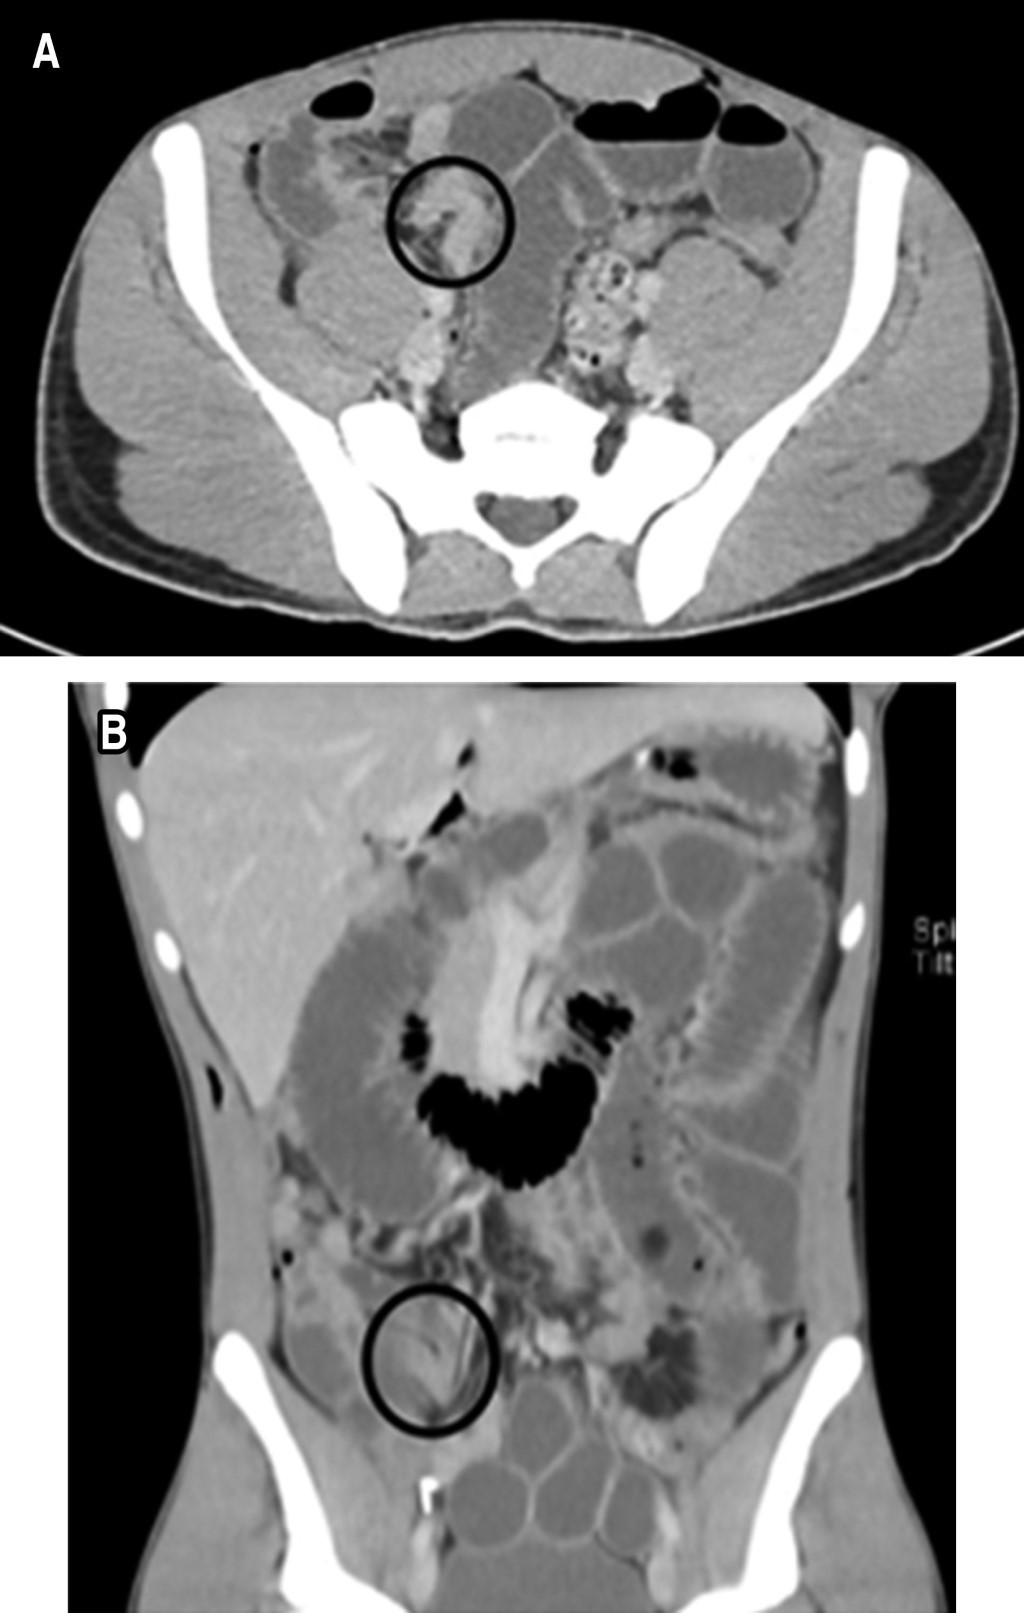

Se ingresó paciente para observación, hidratación por vía intravenosa con solución Ringer lactato y manejo médico sintomático persistiendo con sintomatología, por lo cual se indicó colocación de una sonda nasogástrica (SNG) y una tomografía computarizada (TC) de abdomen con contraste intravenoso. La TC de abdomen demostró obstrucción de intestino delgado con sospecha de hernia interna (Figura 1). Basado en hallazgos clínicos y radiológicos, se decidió realizar una laparoscopia diagnóstica de emergencia. Se identificó como origen de la obstrucción un asa de intestino delgado herniada en el espacio preperitoneal a través de un defecto peritoneal (Figura 2). No se identificaron datos de sufrimiento de asa, por lo cual se redujo la hernia y posterior cierre del defecto del peritoneo con poliglactina 910 2-0 puntos cruzados.

Figura 1